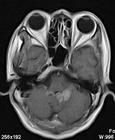

2、MR表現:

①最常見於松果體區,也常見於鞍上,可同時或單獨存在。

②T1加權為略低信號或等信號,T2加權常呈等信號或高信號。

③增強後;呈明顯均勻一致強化,並能發現沿腦脊液或室管膜轉移的病灶。

4.MRI 檢查:MRI 對顯示鞍上小的生殖細胞瘤(直徑<1cm)或脊髓轉移灶十分清楚;顯示松果體區生殖細胞瘤常為圓形、橢圓形或不規則形,多數T1為等或稍低信號,T2 為稍高信號,少數亦可為等信號;注藥後均勻一致的強化,邊界清楚,有時少數僅呈中度或不均勻強化。有報告20%~58%的生殖細胞瘤有小的囊變,這些囊變由於蛋白性液體或壞死液化所致,通常極小,有時在瘤內有小出血灶,在T1 像為高信號;松果體區者可侵犯中腦和丘腦,在T2 像上有周邊模糊高信號影。MRI 對腫瘤的種植或播散顯示全面,除了T1及T2像的多發病灶顯示清晰,而注藥後病變明顯強化。底節生殖細胞瘤也是T1等或低信號,而T2稍高信號,注藥後可均勻強化,有的顯示同側皮層有萎縮現象。